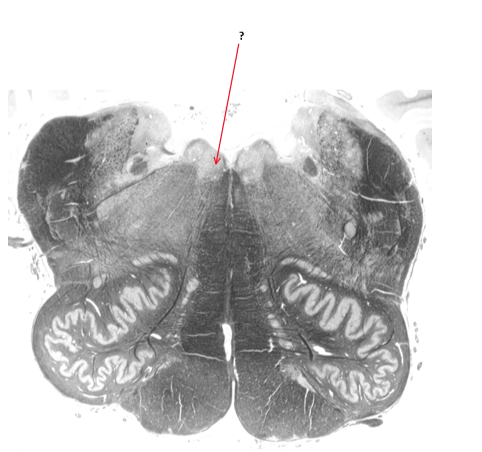

Name this, state its function, divisions and pathway.

Pyramidal tract.

Voluntary control.